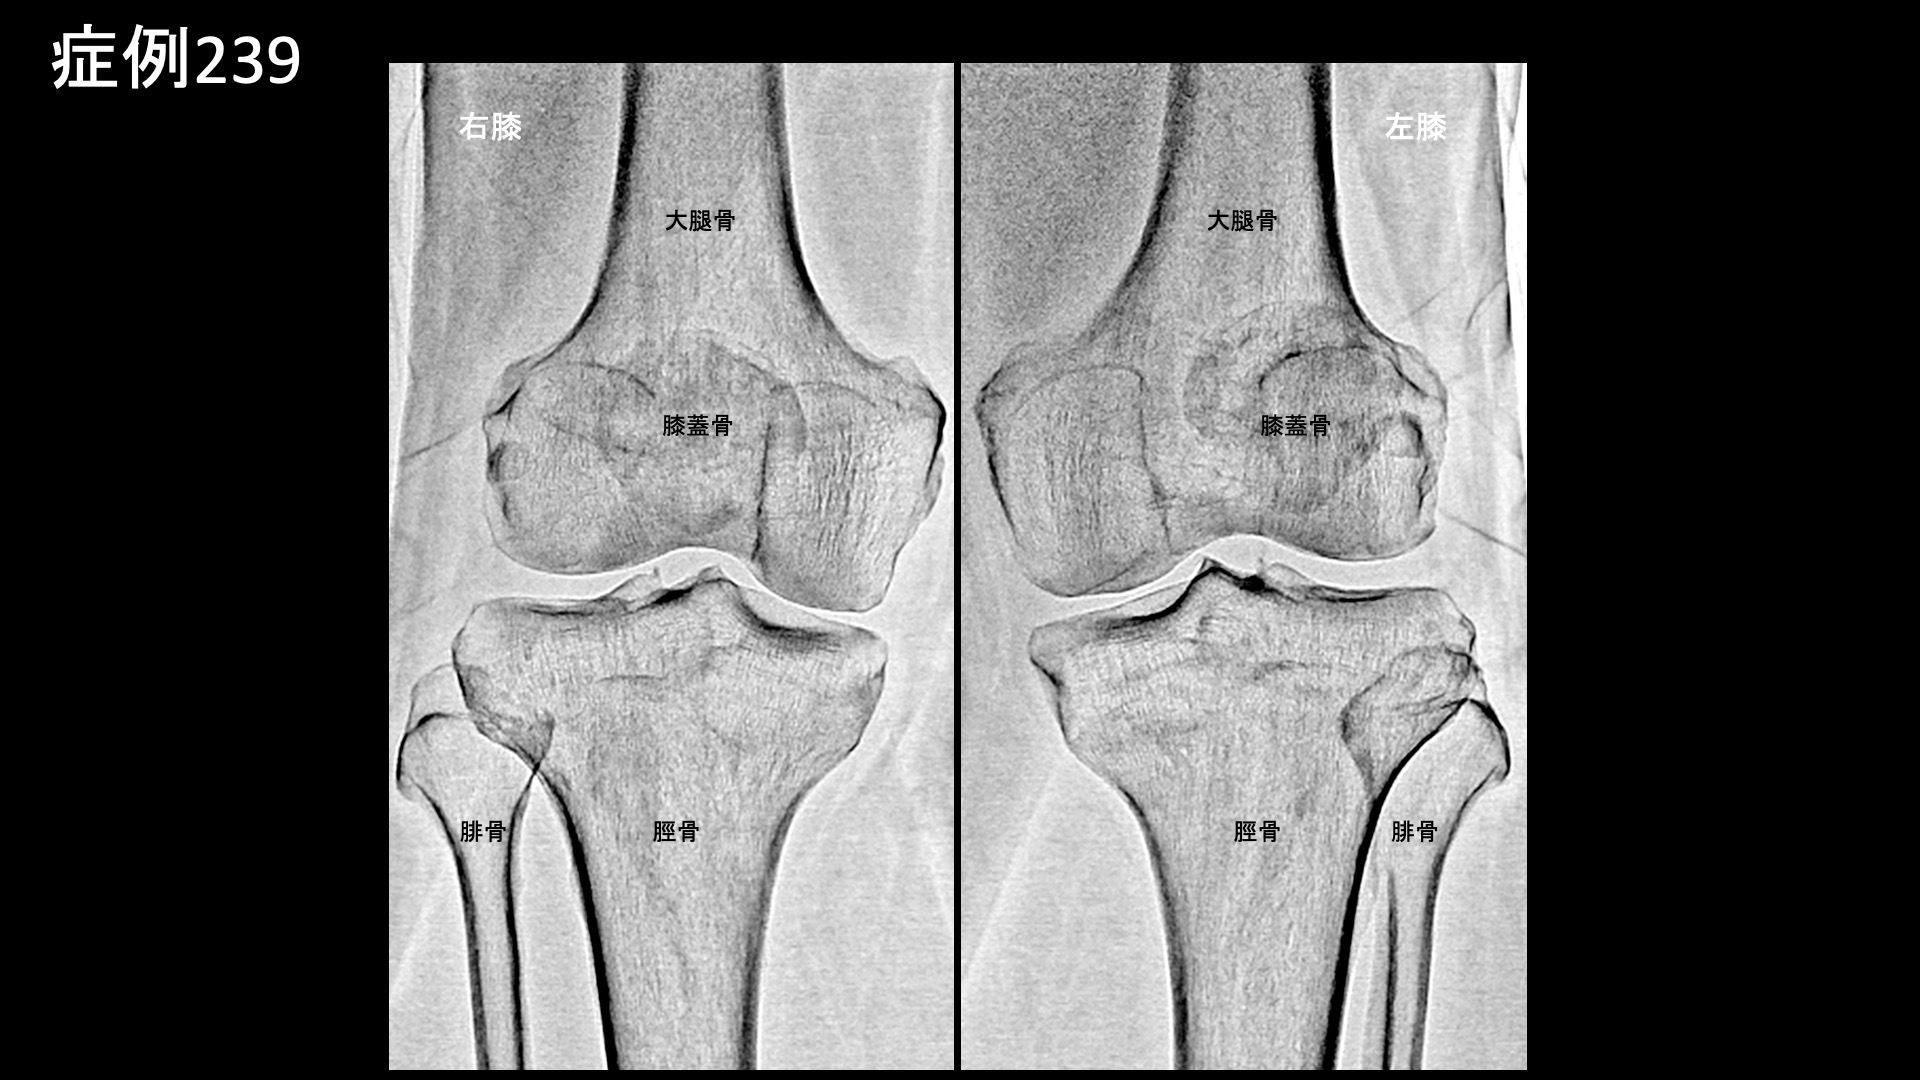

膝:変形性膝関節症など 【70代:男性】夜間痛がその日のうちに改善!強い炎症を伴った変形性膝関節症に対する運動器カテーテル治療(変形性膝関節症) 2025.09.23 鴨井院長による動画解説 受診までの経過 半年前から右膝が痛むようになりました。夜間に疼くようにもなったため、当院を受診しました。 診察時の所見 レントゲンでは両膝関節に中等度以下の変形が見られました(KL分類2/4程度)。両足は扁平足でした。エコーでも同様に中等度までの変形にとどまっていましたが、一方で、異常血流信号は非常に旺盛にみられ、強い炎症が示唆されました。 良い治療適応と判断し、モヤモヤ血管(病的新生血管)に対する運動器カテーテル治療(微細動脈塞栓術)を受けていただきました。 治療の所見 血管造影を行うと、左右とも全周性にモヤモヤ血管が濃染像として描出されました(写真は、下行膝動脈、内側下膝動脈、外側下膝動脈の各血管造影について掲載)。やはり、強い炎症を反映した所見でした。治療後は画像上速やかに消失しました。 治療後の経過 治療直後から症状が改善し、ほぼ痛みが無くなりました。帰り道にも既に違いを実感し、その日の夜にはいつもじんじんと疼いていた痛みが無くなっていました。治療後1ヶ月の再診時には、奇跡的に良くなっている、こんなにも良くなるものかと驚かれました。これまでと人生観が変わり、何か新しいことを初めてみようかと思えるようになったと言われました。その後も違和感を生じることはあるものの、痛みが再燃することはありませんでした。治療後3ヶ月でも順調に経過されており、終診としました。 通常の変形性膝関節症ではもう少し時間をかけて改善することが多いのですが、非常に早期から改善しました。モヤモヤ血管(病的新生血管)に対する運動器カテーテル治療(微細動脈塞栓術)は、炎症が強いほど早期から改善が得られる傾向がありますが、まさにそうした症例でした(夜間痛も強い炎症を反映した臨床所見の一つです)。まだ変形が高度に進行していない内に治療を受けていただけたことも、良い結果が得られた要因です。カテーテル治療の強みを最大限に生かすためには、高度の変形にまで進行する前にご検討いただくとよいと思います。 膝の痛みについては、何とか歩けるうちは医療機関を受診しないという方も多く、受診を決断した時には既に変形が高度に進行していたということも少なくありません。変形性関節症は進行性の病気であり、加齢によっても進行しますが、進行するほど種々の治療が効きにくくなってしまいます。ある程度までの状態でしっかりと治し、その後の進行を予防するための靴・インソール調整、筋力トレーニングなどに取り組み、日常生活についても指導を受けた方が、結果的には長く自分の足で健康に歩くことができますので早めに対処していただくことをおすすめします。昨今では、レントゲンに加えてMRI検査まで受けずともエコー検査である程度の詳細な状態を把握することができますし、そうした医療機関が増えてきています。エコー検査は気軽に受けられますので、状態に応じて、時々チェックを受けるのも良いと思います。 変形性膝関節症の詳しい病状説明はこちら 【80代:女性】新型コロナウイルス感染を契機に悪化した変形性腰椎症による腰痛/坐骨神経痛(新型コロナウイルス感染、変形性腰椎症、腰痛、坐骨神経痛) 前の記事 【10代:男性】恥骨が痛くて走れない、スポーツが原因で生じた恥骨結合炎に対するモヤモヤ血管治療(恥骨結合炎) 次の記事